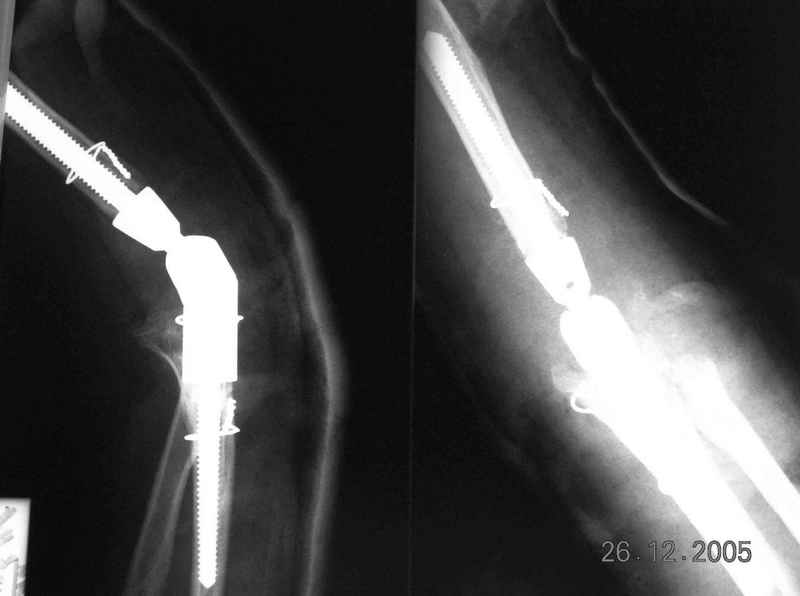

Уважаемый Ильдар, в ноябре 2005 г. мы оперировали практически полностью идентичную ситуацию у больного с гемофилией, поставили модифицированный

эндопротез локтевого сустава типа Сиваша с хорошим результатом. На заводе-производителе (в нашем случае - завод ЦИТО, но есть еще ООО

Эндосервис т/ф (095) 221-06-18, 500-41-30, 513-54-32 ) можно заказать протез этого типа по индивидуальным размерам для восполнения дефицита длины плечевой кости. Сейчас есть и более дорогие коммерческие эндопротезы фирмы Stryker. Наиболее активно оперируют локоть в ЦИТО, у нас тоже есть

собственный небольшой опыт эндопротезирования локтевого сустава.